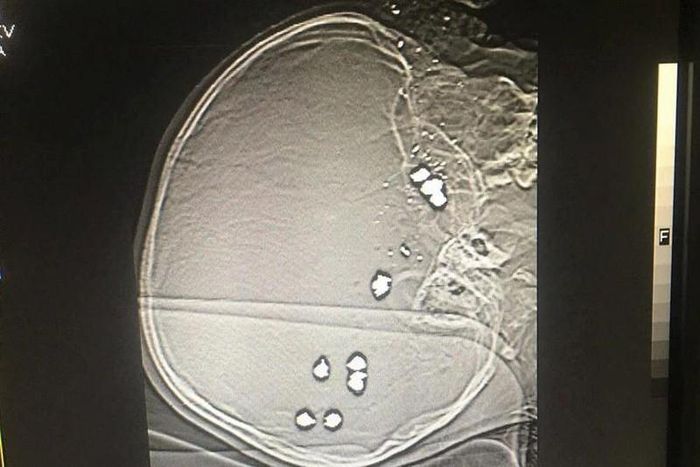

Tiến hành xét nghiệm, chụp chiếu, bác sĩ phát hiện trong đầu cháu P. có 11 viên đạn bi, không còn khả năng cứu chữa... Gia đình cháu B.T.P làm thủ tục để đưa cháu về nhà và cháu P đã tử vong sau đó.

Hình ảnh chụp X-quang cho thấy cháu bé bị nhiều viên đạn găm vào đầu (Ảnh: Bệnh viện Sản Nhi tỉnh Ninh).